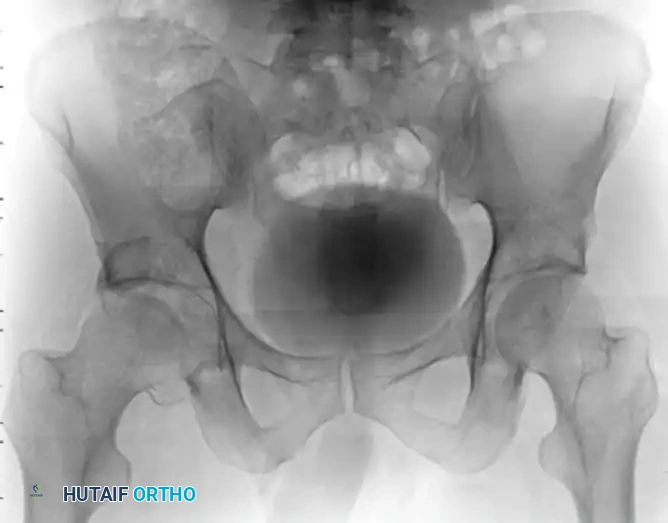

Figure 55-61A: Preoperative radiograph demonstrating a complex Pipkin IV fracture (posterior wall acetabular fracture with an associated femoral head fracture).

Figure 55-61B: Postoperative radiograph following surgical dislocation of the hip, open reduction and internal fixation of the posterior wall acetabular fracture, and débridement of the infrafoveal femoral head fracture.

Figure 55-61E: Postoperative AP pelvic radiograph showing the final construct.